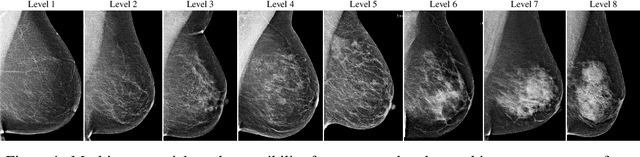

Abstract:Interval and large invasive breast cancers, which are associated with worse prognosis than other cancers, are usually detected at a late stage due to false negative assessments of screening mammograms. The missed screening-time detection is commonly caused by the tumor being obscured by its surrounding breast tissues, a phenomenon called masking. To study and benchmark mammographic masking of cancer, in this work we introduce CSAW-M, the largest public mammographic dataset, collected from over 10,000 individuals and annotated with potential masking. In contrast to the previous approaches which measure breast image density as a proxy, our dataset directly provides annotations of masking potential assessments from five specialists. We also trained deep learning models on CSAW-M to estimate the masking level and showed that the estimated masking is significantly more predictive of screening participants diagnosed with interval and large invasive cancers -- without being explicitly trained for these tasks -- than its breast density counterparts.